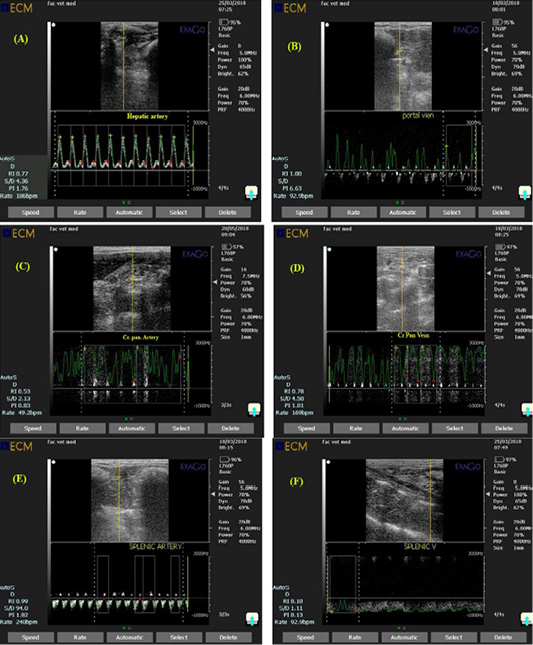

Ultrasonogram showing pulsed wave doppler mode of rabbit hepatic artery (A), portal vein (B), Cranial pancreaticoduodenal artery (C), Cranial pancreaticoduodenal vein (D), splenic artery (E) and Splenic vein (F) with a a gate opened in the known artery to measure amount of blood flow and a gate opened in the known vein to measure amount of blood drainage.